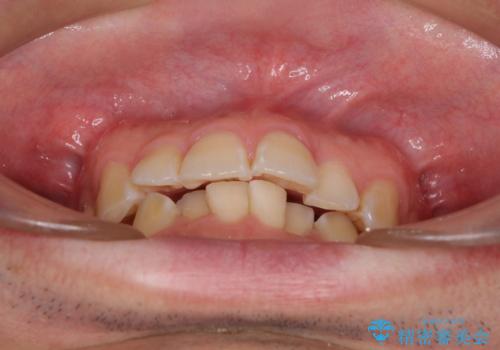

ディープバイトと叢生を解消 インビザライン矯正

- 前歯のデコボコを強い咬みしめを気にして来院された患者様です。

インビザラインを用いて、前歯の叢生を解消するとともに、ディープバイトを改善していくこととしました。

ディープバイトが改善されたことで、顎への負担が軽減され、更には上顎前歯の突出感も改善することができました。